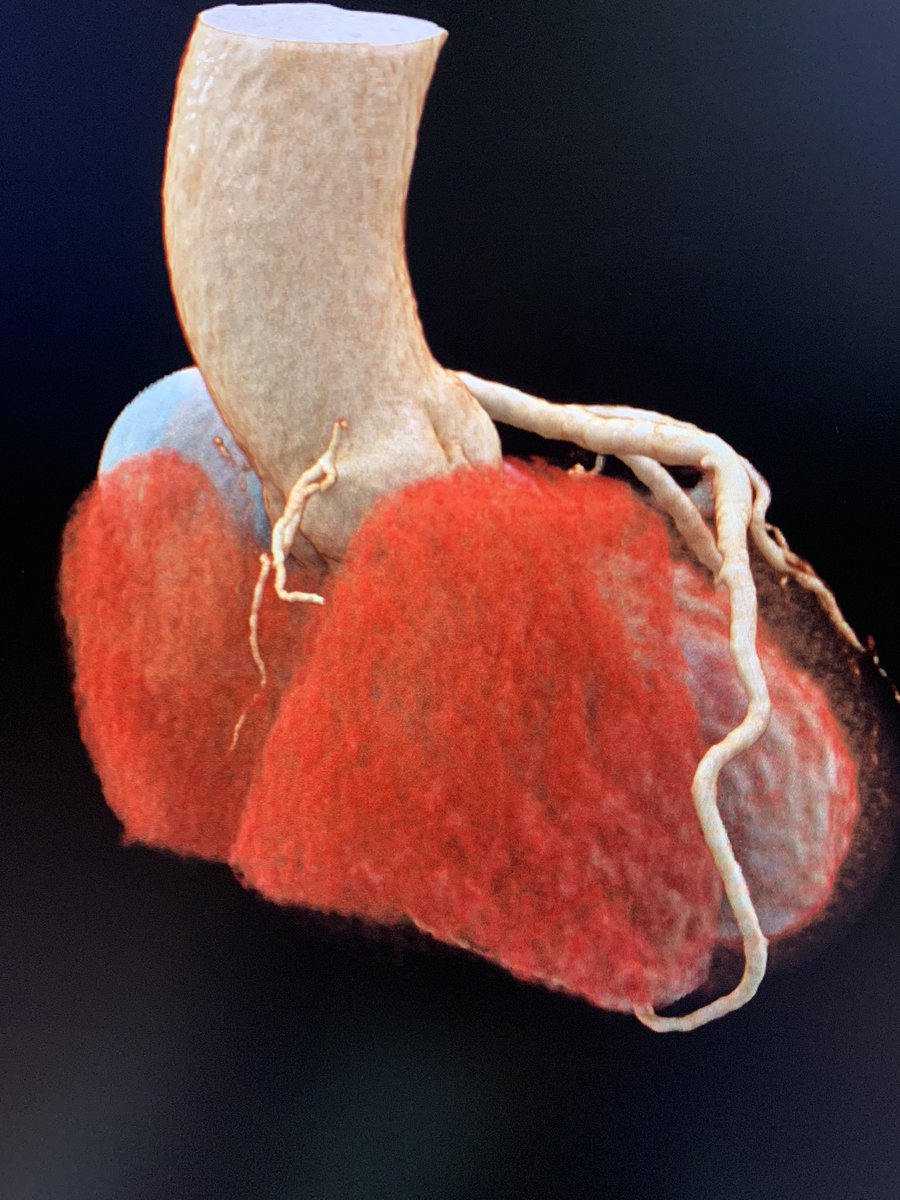

Hyperdominant left anterior descending artery (LAD): A rare coronary anomaly #yesSCCT @ACHA_Heart @Heart_SCCT @FiRSTSCCT